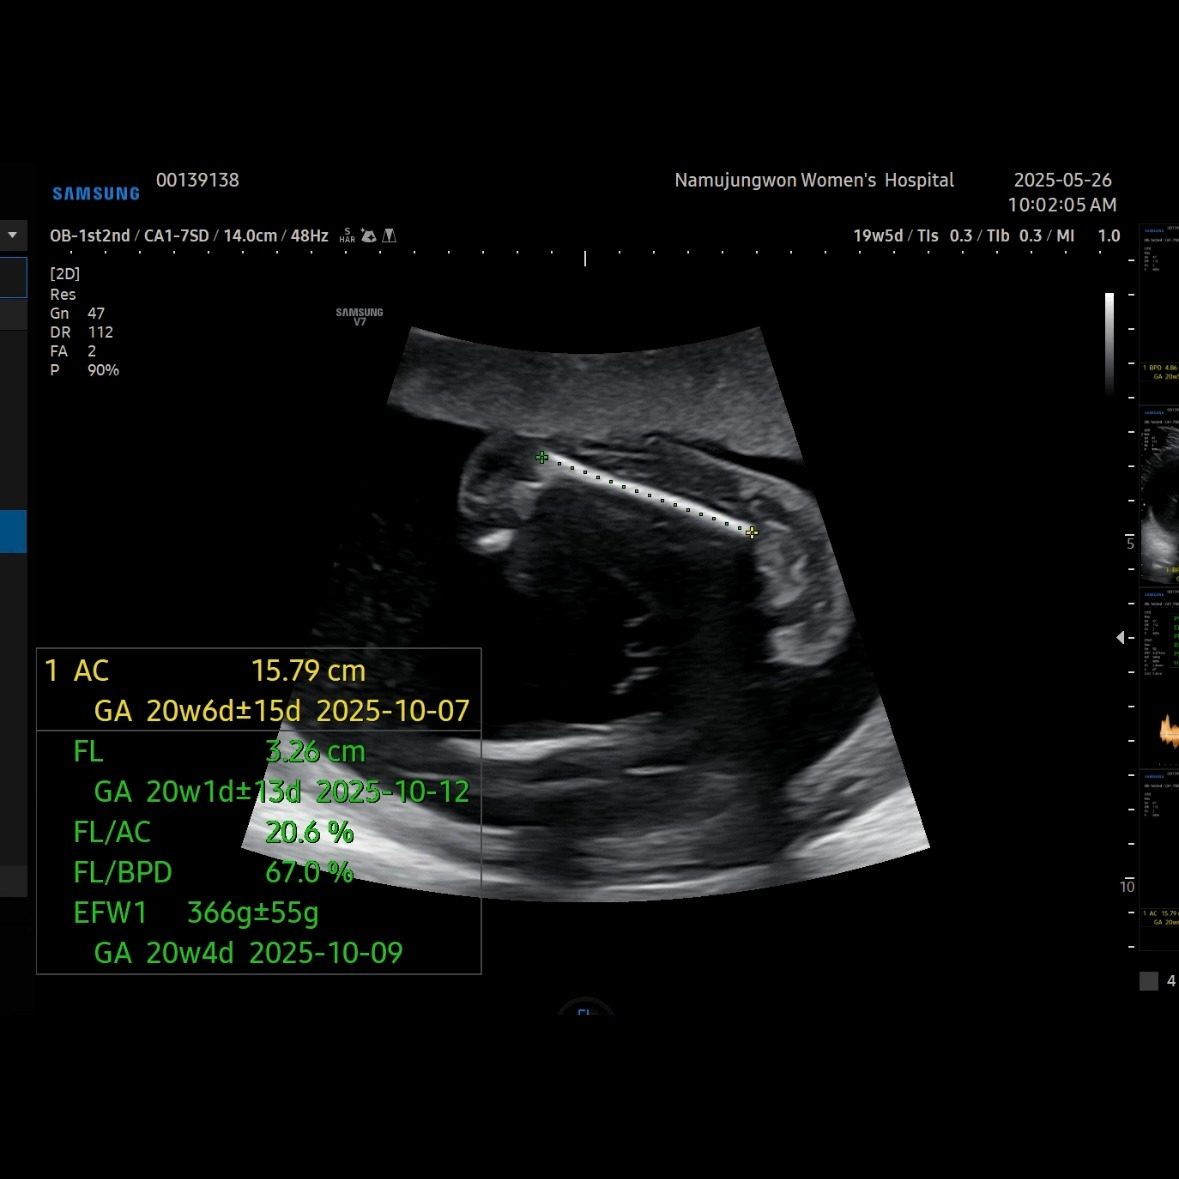

유민이 19주 5일 차에 보러 간 초음파

초음파를 보면 머리둘레, 배둘레, 허벅지 뼈길이를 꼭 재보는 데 유민이는 갈 때마다 1주 정도씩 평균보다 크게 측정된다. 1-2주 크기차이는 의미 없다고 괜찮다고 했다.

이제 얼굴이 형태가 많이 보인다. 코랑 입 위주로 보여줬다. 눈 쪽으로는 손을 올리고 있었다. 이렇게 보면 장기나 뇌나 얼굴이나 대부분 만들어져서 꽤 클 것 같이 생각되지만, 아직까지 400g이 안 되는 무게였다.